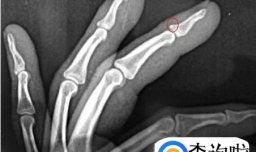

手指骨折怎么做康复训练